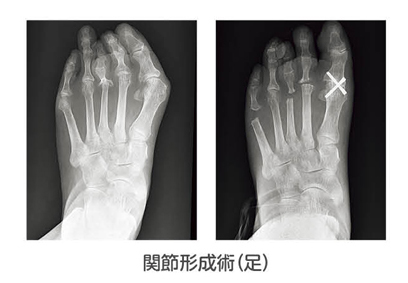

関節形成術

初期~中期において、関節構造を可能な限り残しつつ、関節の機能改善をはかるもので近年増加傾向です。主に肘・手首・指・足趾の関節で行われます。